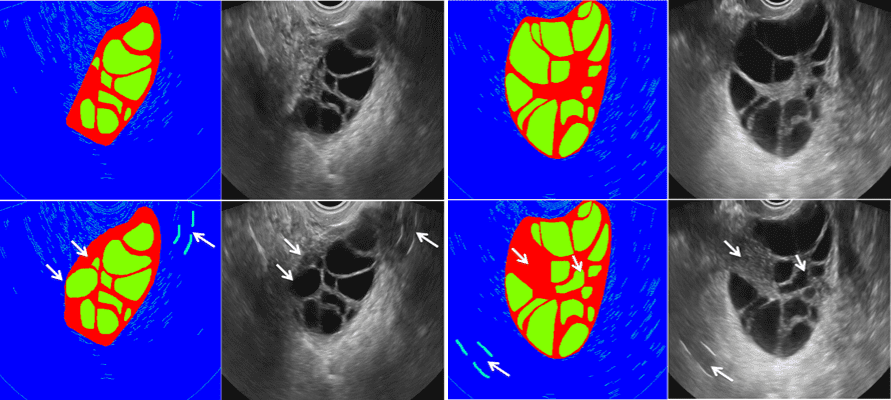

Refer to caption

Fig. 5: Customized synthesis of ovarian US images based on label edition. First/second row: before/after editing.

Fig. 4 visualizes the comparison of generated US images from different methods. Some defects such as background distortion (a,b), checkerboard artifacts (c) and stretching effects (d) are denoted by arrows in Fig. 4. In contrast, our method generates more realistic synthesized images. Furthermore, our method enables not only synthesizing images from real labels but also being capable to generate images using edited labels (see Fig. 5). By this way, we can create high fidelity ovarian US images with various pathological morphologies. Table 1 further lists the numerical evaluation metrics, including Freshet Inception Distance (FID) [14], Kernel Inception Distance (KID) [15] and multi-scale structural similarity (MS-SSIM) [16]. 8.5 hours was needed for training the resolution of 256 and 16 hours for resolution of 512. For testing phase, it took only 0.07s for an image generation in GPU and 5.58s in CPU on average. Our method outperformes all other compared methods with regard to all metrics, which is mainly due to the employment of auxiliary sketch and progressive training scheme.